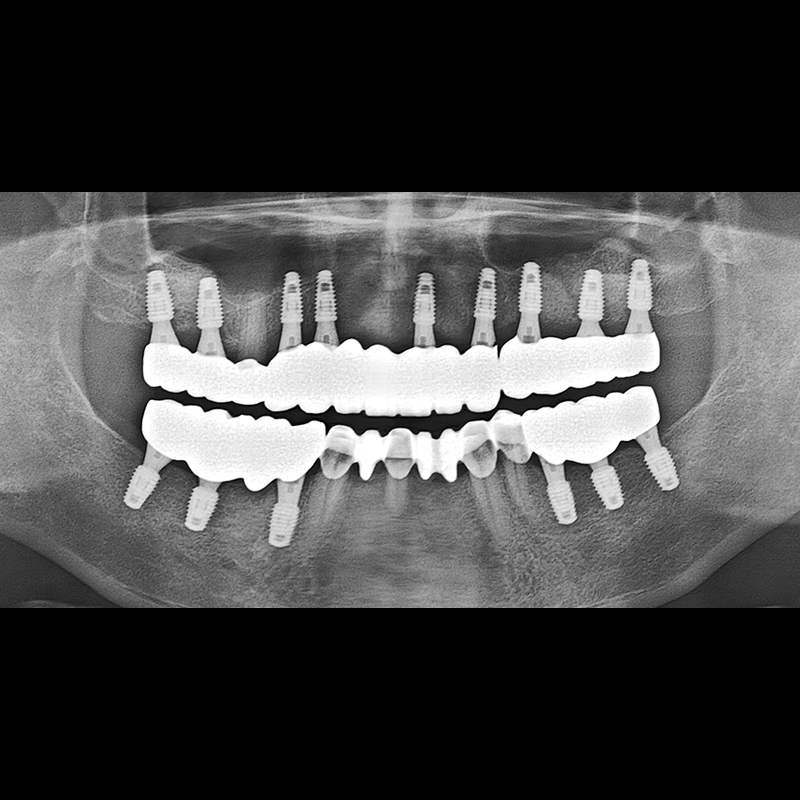

BEFORE AFTER

임플란트 전후사진 2025.05.30

결손된 치아 부분과 살리기 힘든 치아 위치에 임플란트를 식립하였습니다.